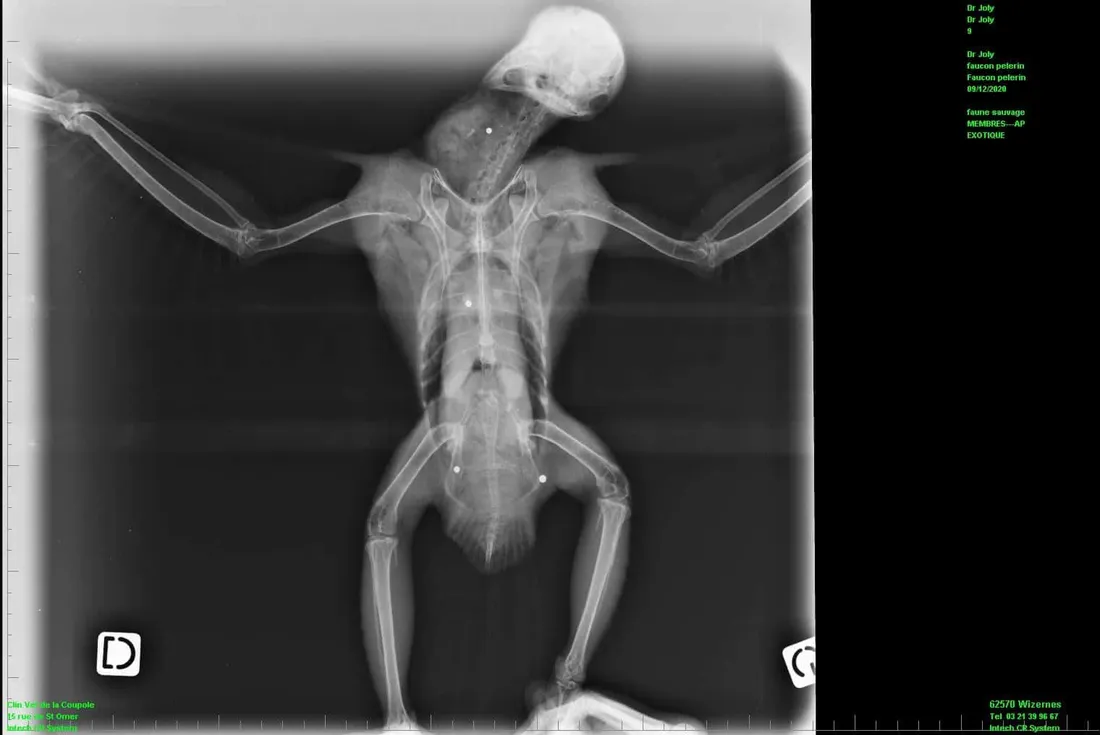

Un nouvel oiseau, une espèce protégée, a été plombé. On vous parlait d’une buse blessée dans le marais le week-end dernier. Cette fois, il s’agit d’un faucon pèlerin retrouvé criblé de plombs dans le centre-ville d’Aire-sur-la-Lys ce mercredi 09 décembre. Quatre plombs ont été retrouvés sur le corps de l’oiseau. Impossible de les retirer, l’opération serait trop risquée. Impossible de savoir s’il pourra retrouver la liberté un jour selon les séquelles qu’il lui restera. Une nouvelle fois, la Ligue de Protection des Oiseaux du Pas de Calais va porter plainte. C’est le 14ème oiseau protégé victime de tirs de plombs depuis l’ouverture de la chasse en septembre.